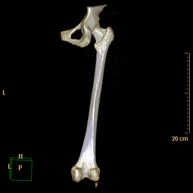

Exploració radiològica que mitjançant un sistema de raigs X i detectors que giren al voltant del pacient i que reconstrueixen les imatges per ordinador (TC Multidetector), permet calcular una sèrie de mesures a nivell de maluc, genolls i turmells per solucionar problemes de rotació i angulació de les extremitats inferiors. - TC d'ossos llargs

Exploració radiològica que mitjançant un sistema de raigs X i detectors que giren al voltant del pacient i que reconstrueixen les imatges per ordinador (TC Multidetector), permet l'estudi detallat dels ossos llargs (tíbia, peroné, fèmur, húmer, radi i cúbit). - Biòpsia òssia guiada per TC